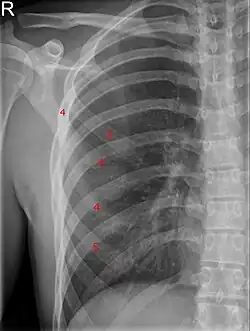

Die Gabelrippe ist eine Normvariante des menschlichen Skeletts, bei der sich die Rippe im vorderen Anteil in zwei Enden aufgabelt, daher die Bezeichnung. Sie ist eine von zahlreichen möglichen Fehlbildungen der Rippen und wird in ihrer klassischen Form auch als Luschka-Gabelrippe bezeichnet.

Bei schlanken Personen, insbesondere Kindern, ist sie fast immer im vorderen Brustkorbbereich tastbar. Da für eine überzählige Rippe nicht genug Platz da ist, kommt es meistens zu umschriebenen Vorwölbungen, die bis zum Ende der Wachstumsphase mitwachsen. Sofern diese Aufgabelung im knöchernen Rippenanteil liegt, kann sie auf dem Röntgenbild dargestellt werden bzw. als Schatten auffallen. Bei Lage der Gabelung im Knorpel kann dieses sehr einfach mit Ultraschall nachgewiesen werden. Meistens schon klinisch gut zu unterscheiden sind Exostosen und alte Rippenbrüche.